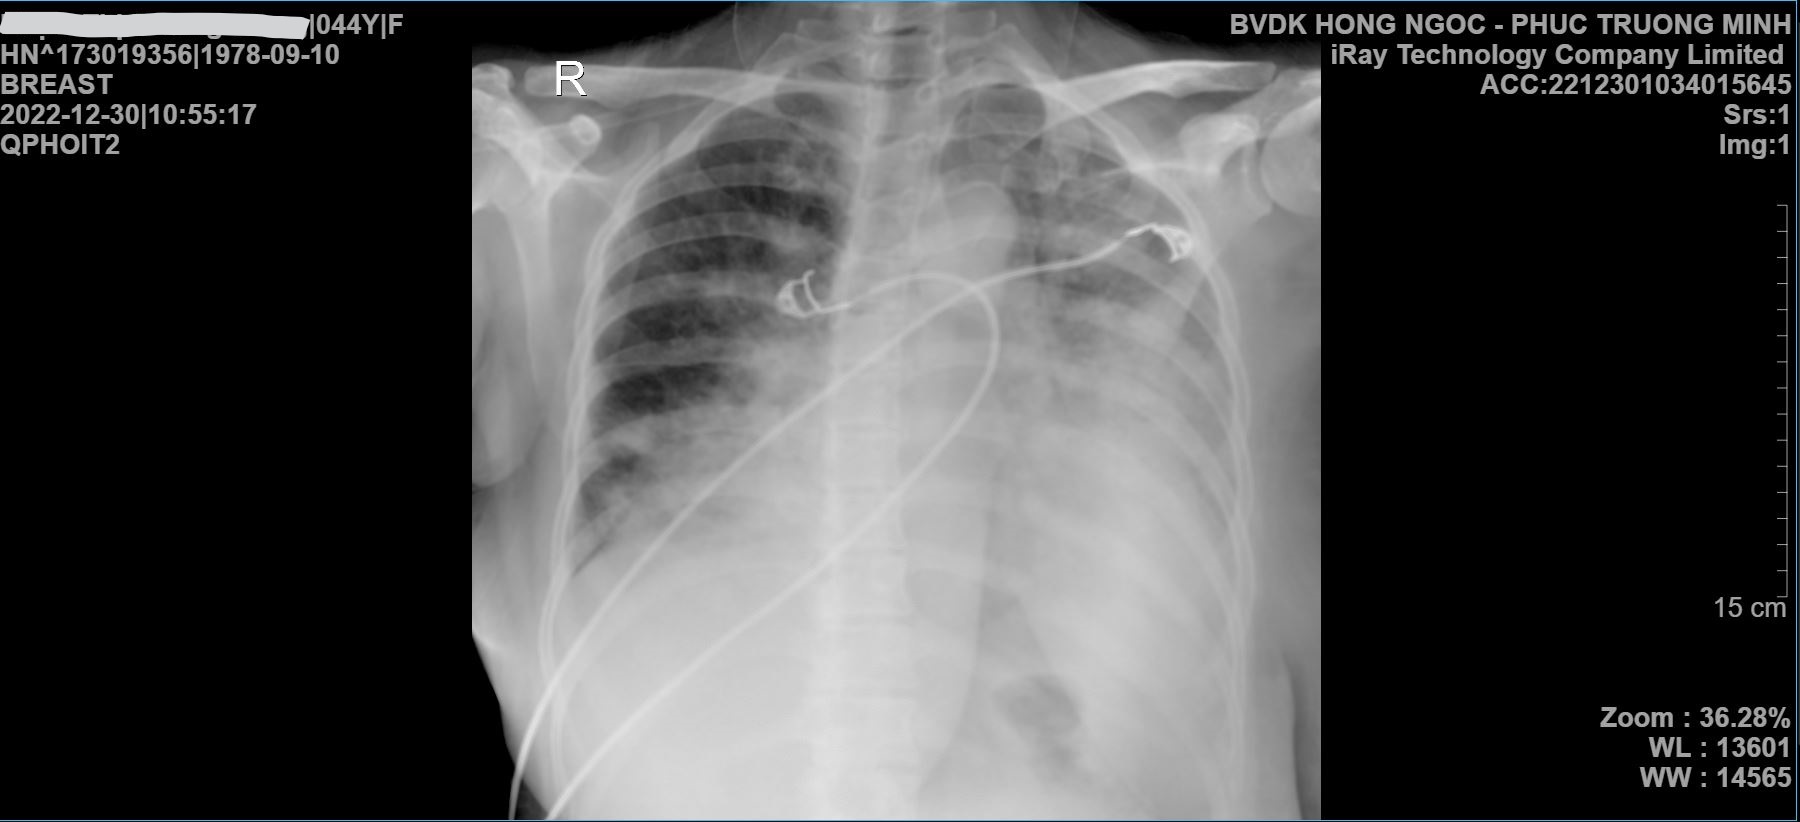

Chụp Xquang phổi Kết quả chụp Xquang phổi của bệnh nhân sau 5 ngày nhập viện điều trị, phổi đã sáng hơn

Sau đặt nội ống khí quản, thở máy, bệnh nhân luôn được chăm sóc và theo dõi sát sao từng chỉ số. Và chỉ sau 3 ngày áp dụng phác đồ điều trị tích cực bệnh nhân đã cai được máy thở, đi lại bình thường, phổi hồi phục và tiên lượng tốt. Sau 7 ngày lưu viện, sức khỏe của bệnh nhân tiến triển tốt, giảm ho, ăn uống ngon miệng.